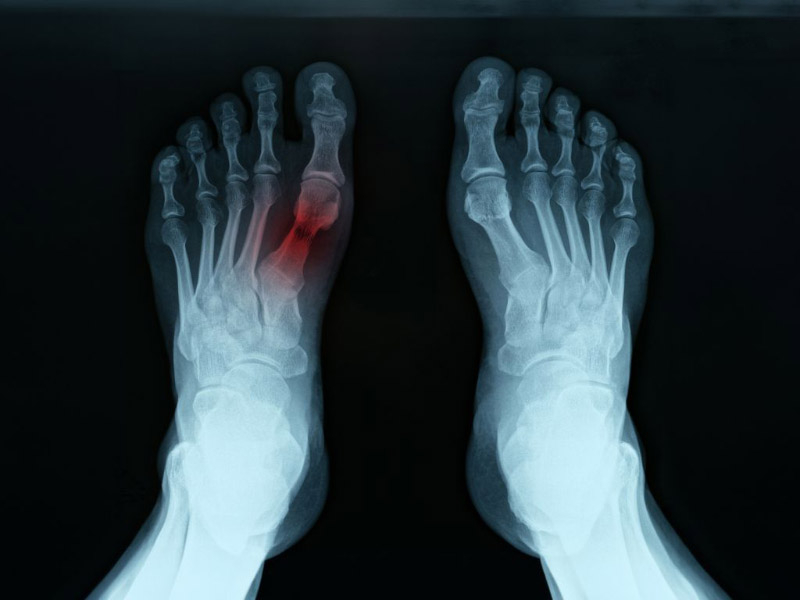

• Chụp X-quang: Phương pháp này giúp quan sát tình trạng sụn và xương ở ngón chân cái. Người bệnh có thể được yêu cầu chụp x-quang đứng để đánh giá chính xác ảnh hưởng của trọng lượng cơ thể lên khớp chân.

chụp xquang phát hiện viêm khớp ở ngón chân

Chụp x quang là một trong những bước chẩn đoán viêm khớp ngón chân cái